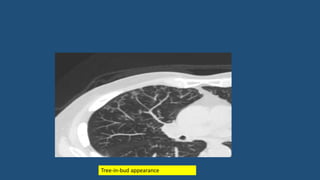

Tree-in-bud appearance

• Tree-in-bud describes the appearance of an irregular and often nodular branching

structure, most easily identified in the lung periphery.

• It represents dilated and impacted (mucus or pus-filled) centrilobular

bronchioles.